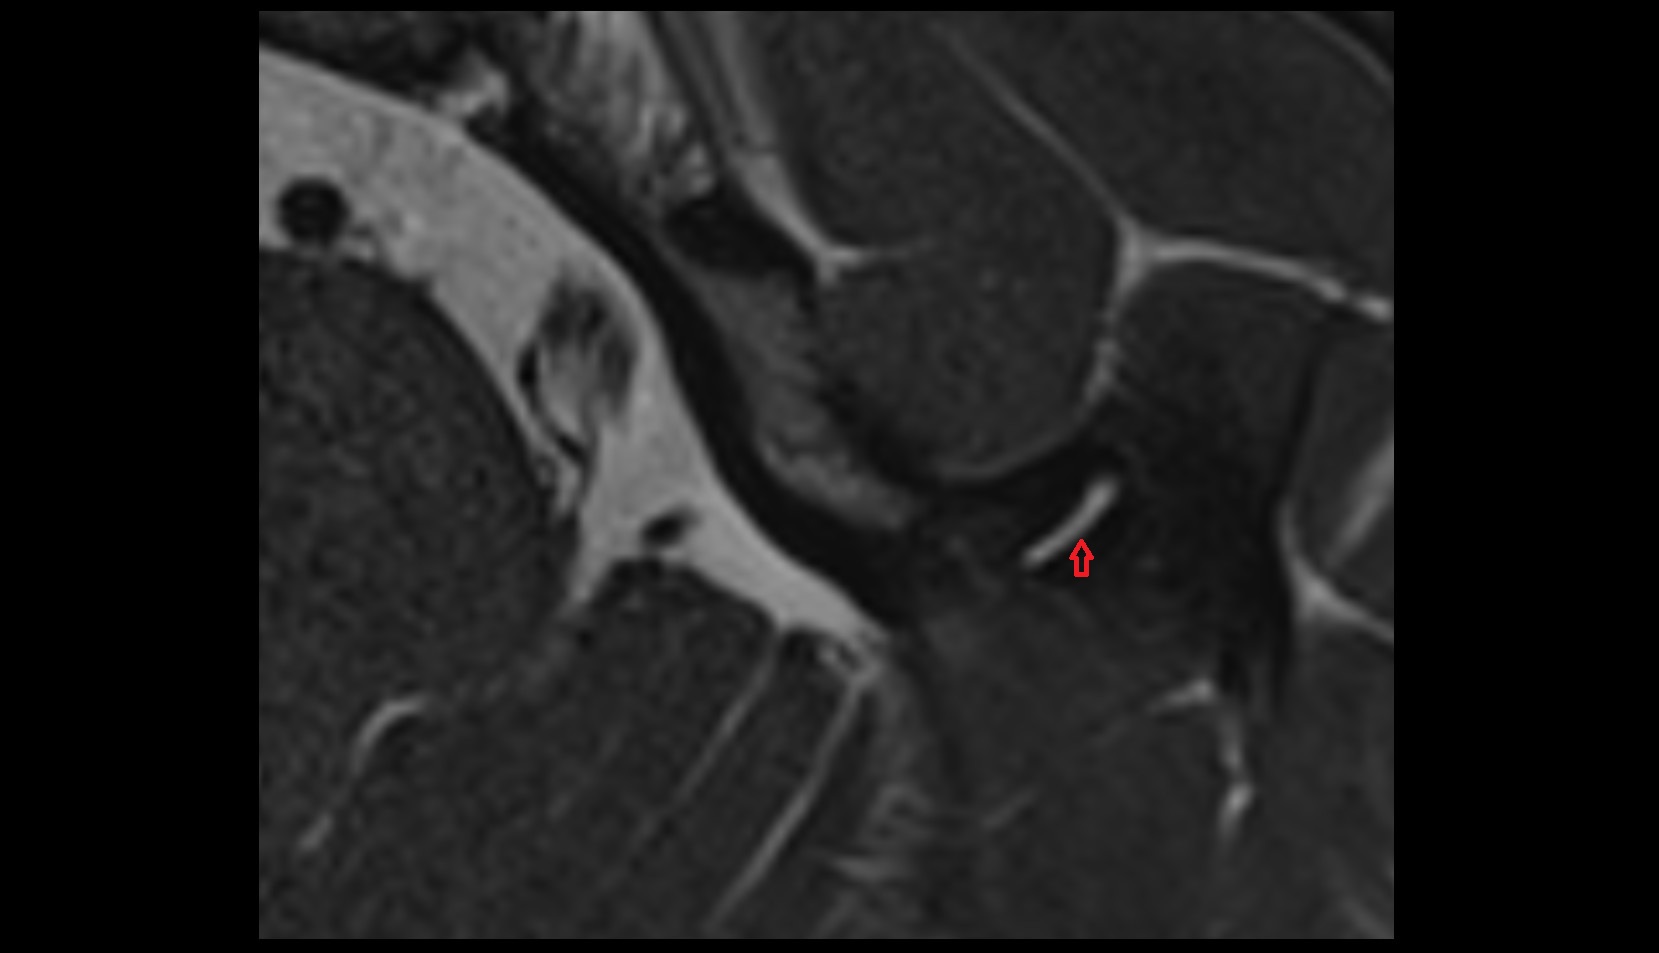

- Temporomandibular joint

- Articular disc of temporomandibular joint

- Mandibular condyle

- Mandibular fossa

- Articular eminence